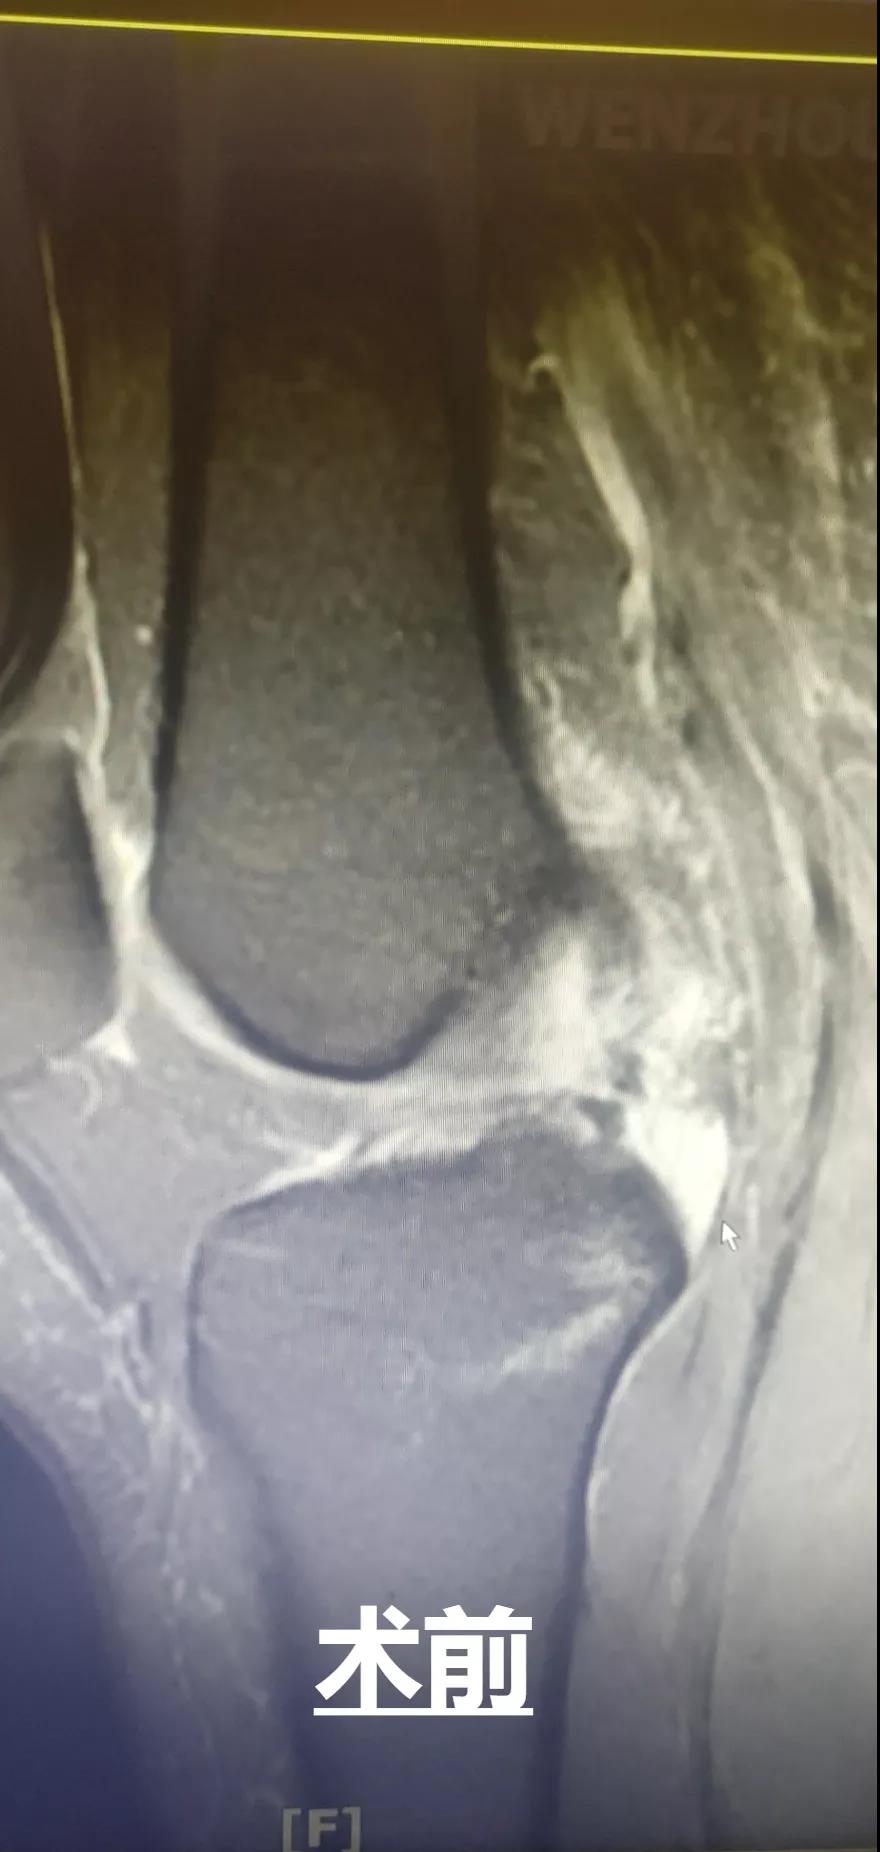

此外,和平國(guó)際醫(yī)院關(guān)節(jié)鏡微創(chuàng)團(tuán)隊(duì)還完成了一例交叉韌帶修復(fù)術(shù)。此手術(shù)采用三個(gè)約0.5cm的微小創(chuàng)口,于脛骨結(jié)節(jié)處進(jìn)行定位,后鉆通脛骨隧道,應(yīng)用多種袢鈦板進(jìn)行多位置固定,手術(shù)過(guò)程短,創(chuàng)口小,術(shù)后效果好,患者十分滿意。